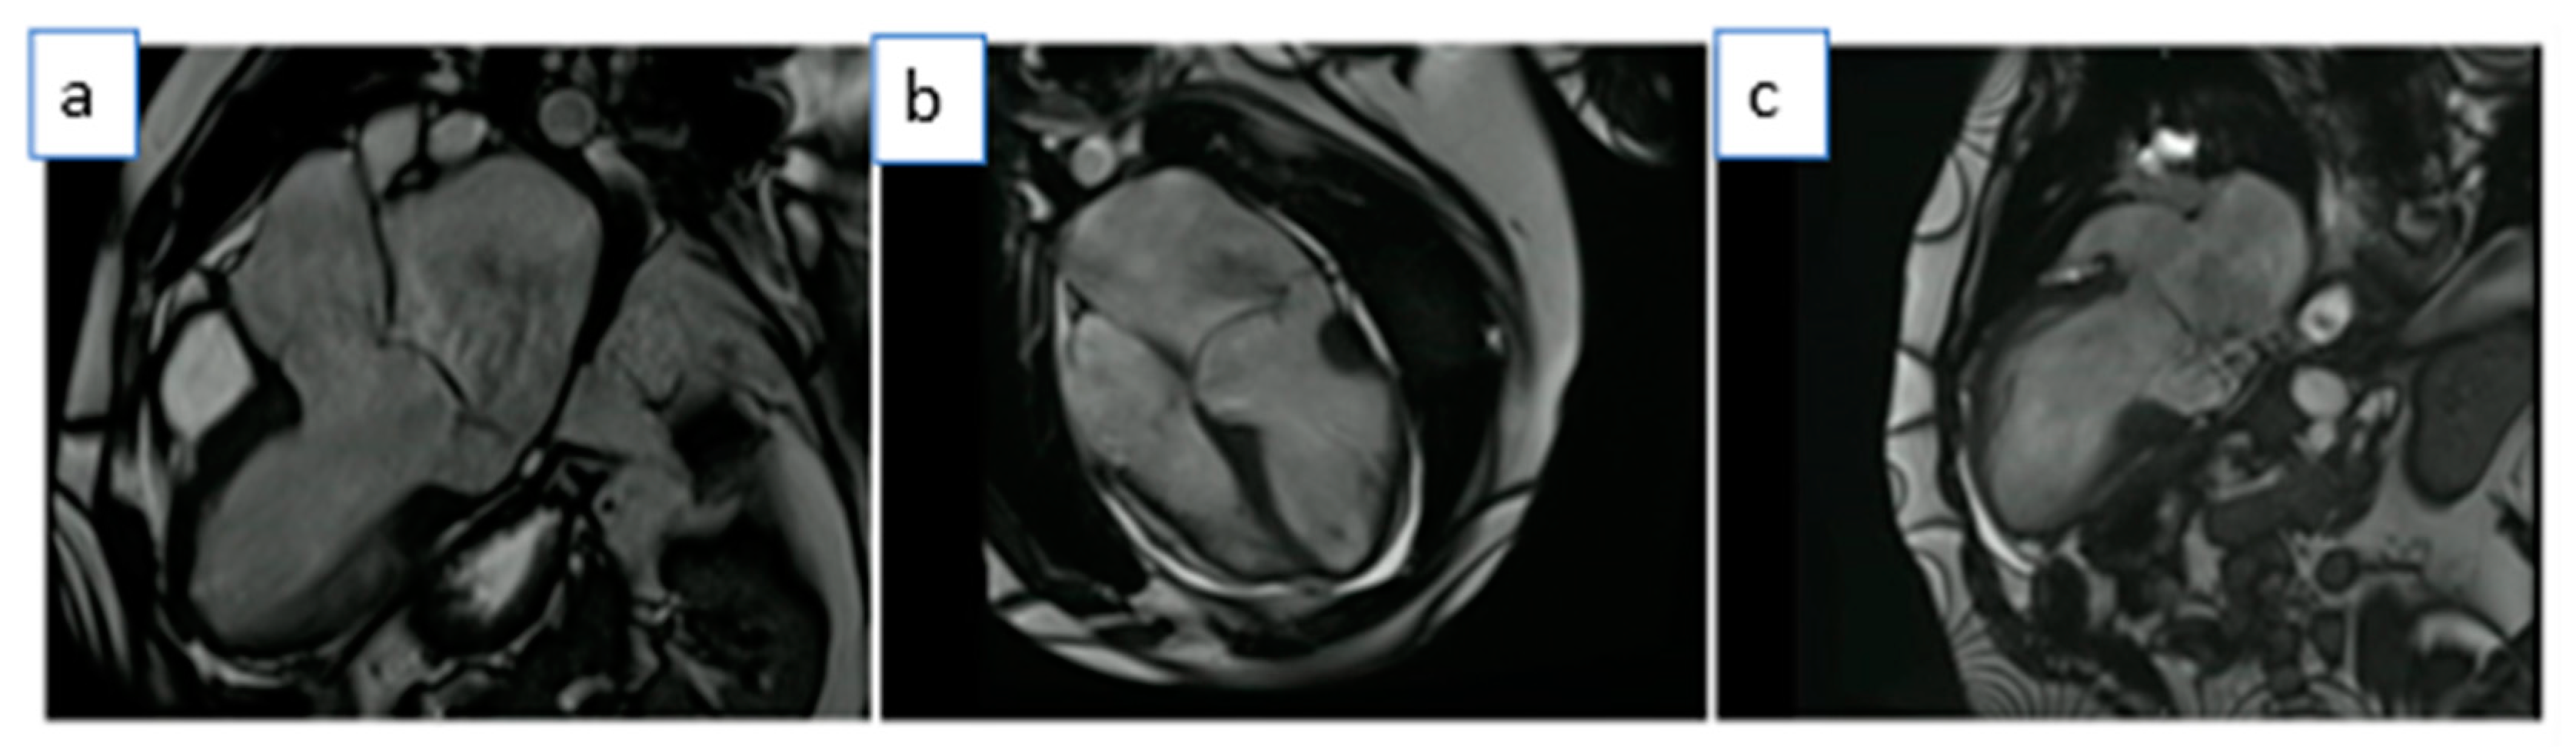

There was bileaflet mitral valve prolapse (MVP) with redundant mitral valve leaflets and prominent mitral annular disjunction (MAD) was apparent with a maximal disjunction distance of 18.0 mm (Figure 2, Videos S2 and S3).

Figure 2. CMR balanced steady-state free precession (b-SSFP) cines in systole showing mitral annular disjunction (18 mm between arrows): (a). Left ventricular outflow tract (LVOT) view, (b). heart-long-axis (HLA) view, (c). ventricle long-axis (VLA) view.